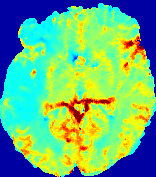

LesionRefer to captionRefer to captionRefer to captionRefer to captionRefer to captionRefer to caption𝐕rgbsubscript𝐕𝑟𝑔𝑏{\bf{V}}_{rgb}Refer to captionRefer to captionRefer to captionRefer to captionRefer to captionRefer to caption𝐕2subscriptnorm𝐕2{\|\bf{V}}\|_{2}Refer to captionRefer to captionRefer to captionRefer to captionRefer to captionRefer to captionRefer to caption3.53.53.52.82.82.82.12.12.11.41.41.40.70.70.70.00.00.0(mm/s)𝑚𝑚𝑠(mm/s)D𝐷DRefer to captionRefer to captionRefer to captionRefer to captionRefer to captionRefer to captionRefer to caption0.0200.0200.0200.0160.0160.0160.0120.0120.0120.0080.0080.0080.0040.0040.0040.0000.0000.000(mm2/s)𝑚superscript𝑚2𝑠(mm^{2}/s)Slice #1Slice #2Slice #3Slice #4Slice #5Slice #6

Figure 4: PIANO feature maps for another patient in the ISLES 2017 training set, where the lesion is located in the right hemisphere. Top row: segmented stroke lesion region (white) on different slices. The corresponding slices for the PIANO feature maps are shown in the following rows.

For a better insight into an estimated velocity field 𝐕𝐕{\bf{V}} and diffusion field 𝐃𝐃{\bf{D}}, we compute the following maps: (1) 𝐕rgbsubscript𝐕𝑟𝑔𝑏{\bf{V}}_{rgb}: Color-coded orientation map of 𝐕=(Vx,Vy,Vz)T𝐕superscriptsuperscript𝑉𝑥superscript𝑉𝑦superscript𝑉𝑧𝑇{\bf{V}}=(V^{x},V^{y},V^{z})^{T}, obtained by normalizing 𝐕𝐕{\bf{V}} to unit length and mapping its 3 components to red, green, blue respectively; (2) 𝐕2subscriptnorm𝐕2\|{\bf{V}}\|_{2}: 222 norm of 𝐕𝐕{\bf{V}}; (3) D𝐷D: scalar field in Eq. 5.

Fig. 3 and Fig. 4 show the PIANO feature maps estimated from two ISLES 2017 patients: all are highly consistent with the lesion in both cases. Details of the blood flow trajectories are revealed in 𝐕rgbsubscript𝐕𝑟𝑔𝑏{\bf{V}}_{rgb} by the ridged patterns and the sharp changes of colors in the unaffected (right) hemisphere, while the flat patterns appearing within the lesion provide little directional information about the velocity and indicate low velocity magnitudes. Velocity magnitudes are more directly visualized via 𝐕2subscriptnorm𝐕2\|{\bf{V}}\|_{2}, from which one can easily locate the lesion where 𝐕2subscriptnorm𝐕2\|{\bf{V}}\|_{2} is low. D𝐷D also indicates lower diffusion values in the lesion, though with less contrast potentially due to the fact that it captures the accumulated effect of CA diffusion at the voxel-level.